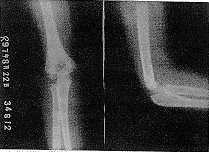

儿童到成人的整个骨发育过程中,无论从外观形态还是X线影像上观察,肱骨下端的变化都是很明显的。从肱骨下端各二次骨化中心依次出现到骨骺行将闭合、骨形态成熟接近成人,一般要到14~17岁才能完成。在儿童期,无论X线影像还是骨标本实际测量(笔者曾进行过骨标本实际测量),其骺软骨以上的骨干部基本没有前倾角,少量的下端外形前倾角是骺软骨二次骨化中心偏前形成的干骺角所致。前倾角是骨发育过程中逐步形成和完善的。以7岁儿童为例,我们实测干骺角为6°~8°,而成人则在30°~50°[3](见图1)。4、9岁及成人肱骨下端X线片前倾角变化(见图2~4)。

图3 9岁儿童肱骨下端X线片

Fig 3 X-ray film of a 9-year-old child's humerus

图2 4岁儿童肱骨下端X线片

Fig 2 X-ray film of a 4-year-old child's humerus